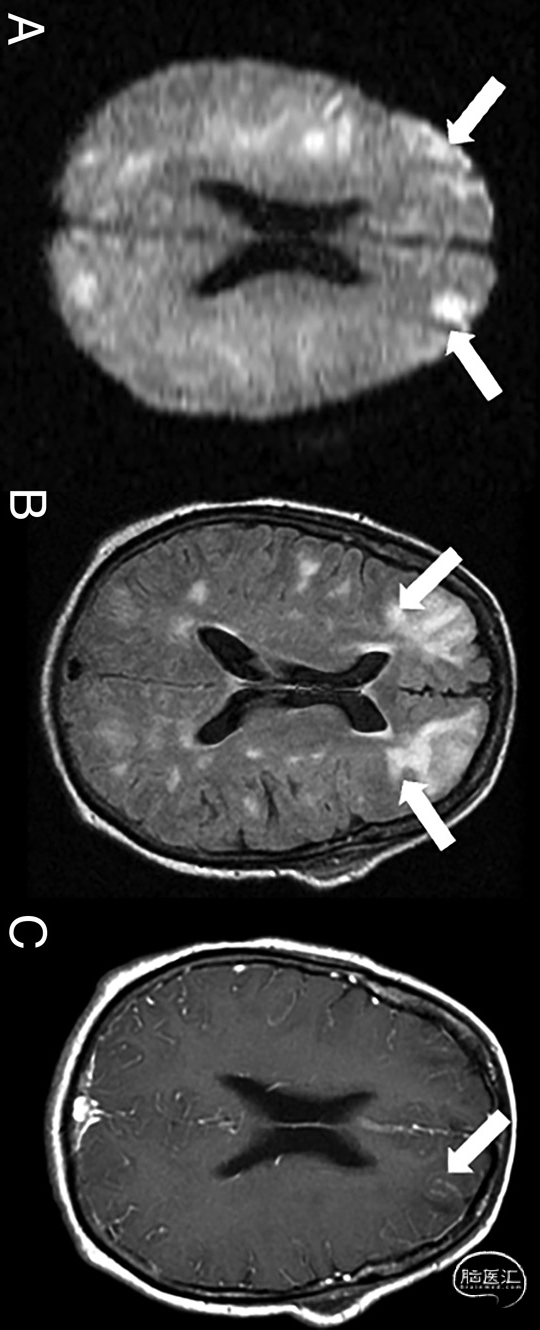

图1. 68岁疑似CAE患者的增强脑MRI。在远端血管床中,呈现细胞毒性水肿(白色箭头,DWI序列,a)和血管源性水肿(白色箭头、T2-FLAIR序列,B)的混合模式,水肿区域附近伴随软脑膜增强(白色箭头;增强后[MultiHance;Bracco Diagnostics]3D gradient-echo T1序列,C):